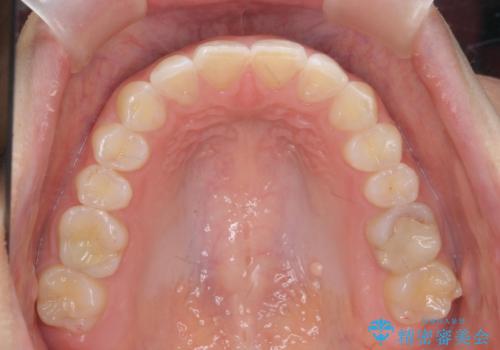

- 下の前歯のがたつきを治したいとのことでした。

上の前歯のちょっとしたねじれも治療しています。

軽度だったため、部分矯正のコースで短期間で治療しました。

下の歯並びを並べるため、わずかに歯を削合しています。

そうしないと、前に出て上の前歯に強く当たってしまうためです。また、後戻りを防ぐ効果もあります。